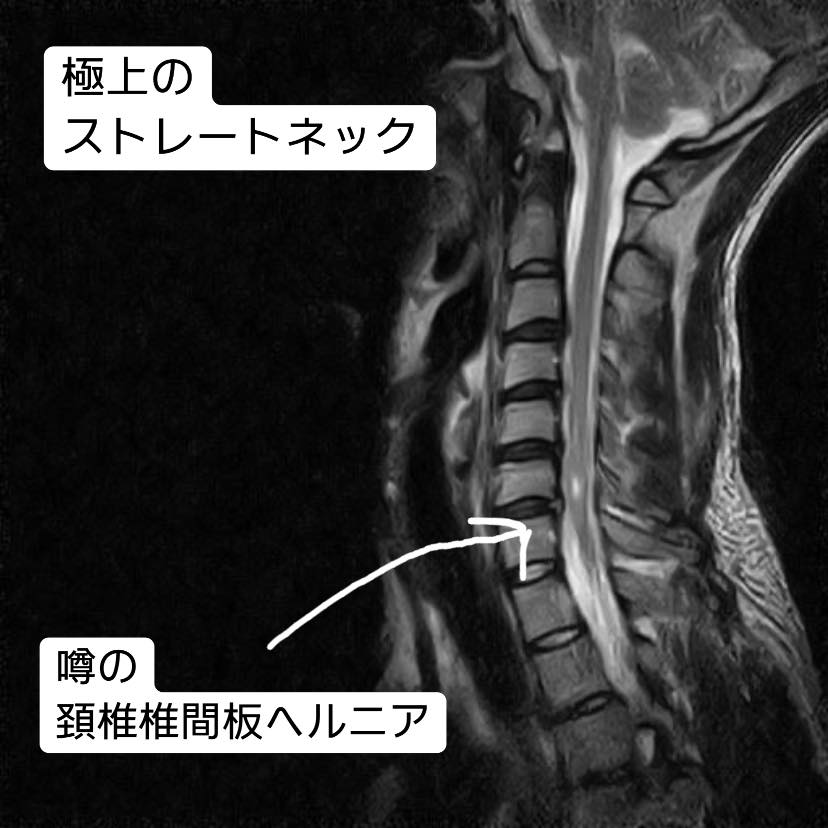

結果は見ての通り、紛うことなき椎間板ヘルニアでした。(普通は見ても分かりませんが![]() )

あ、ヘルニア、っていうのは「本来あるところから、飛び出る」って意味です。

椎間板(にあるべきもの)が飛び出て、脊髄に触れてしまう。ってのが、いわゆる椎間板ヘルニアですね。